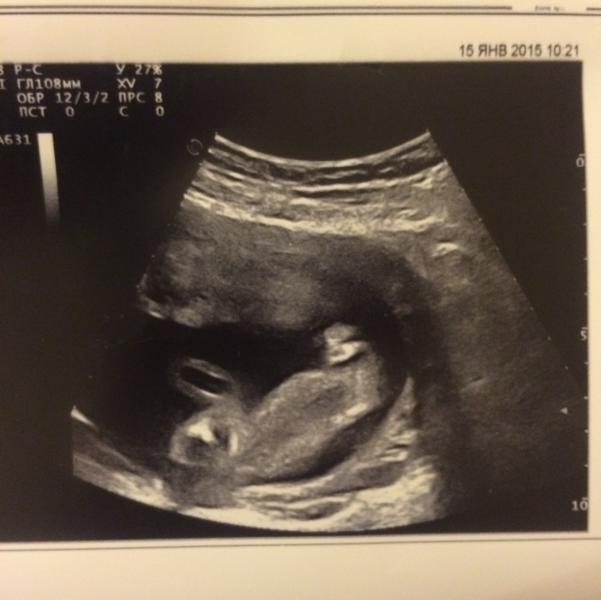

Сходили сегодня на второй скрининг. Наше опережение на 4 дня сохраняется, так что по узи у нас сегодня ровно 24 недели. Но огорошили сегодня, что даже вес и рост забыла спросить...у нас девочка! Чуть придя в себя, обрадовалась. Ведь это бантики, платьица, куклы) А папа наш злится, говорит, вы сначала определитесь там, а потом говорите. Ну я же не причем:) это все врачи (нам в 18 недель сказали, что парень). Короче, буду ждать следующего узи, а ниже фото причинного места: попа справа, вверху прав...